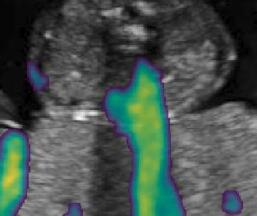

Fig. 6 compares the shadow confidence maps of the state-of-the-art methods and the proposed methods. RW and have the same parameters as used for Table I. The shadow confidence maps of the baseline, the proposed method and the proposedAG method are generated directly from input shadow images by confidence estimation networks. Overall, the proposed method and the proposedAG method achieve more visually reasonable shadow confidence estimation than the baseline and the state-of-the-art on different anatomical structures shown in Fig. 6. The proposed method and the proposedAG method are able to highlight multiple shadow regions while the RW algorithm shows limitations for most cases, especially for disjoint shadow regions.

Row I in Fig. 6 shows a fetal brain image from . The confidence estimation of shadow regions from the baseline, the proposed method and the proposedAG method are similarly accurate since we use fetal brain images to train the confidence estimation networks in these three methods. These outperform [16] and [22]. Rows (II-IV) in Fig. 6 show shadow confidence maps of non-brain anatomy from , including lips, abdominal and cardiac. The baseline failed on unseen data during inference. However, the proposed methods are able to generate accurate shadow confidence maps because of the generalized shadow features obtained by the shadow-seg module. Furthermore, the “Lips” example shows that our method is capable of detecting weaker shadow regions that have not been annotated in manual segmentation. This indicates that the confidence estimation network has learned general properties of shadow regions.